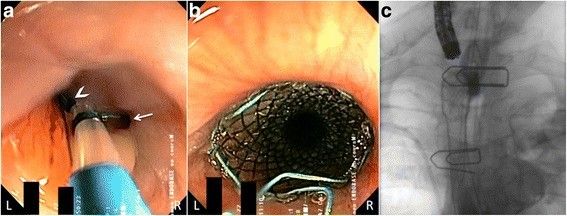

Для коррекции этого состояния выполнена установка покрытого саморасширяющегося металлического стента, верхний край которого расположили чуть ниже верхнего пищеводного сфинктера (рис. 4). Состояние пациента улучшилось в течение двух недель после проведения стентирования.

Рисунок 4 [1].